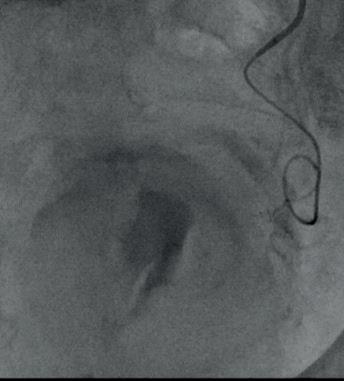

Lohle and colleagues’ study collected prospectively data from 51 patients between September 2023 and January 2025 with symptomatic uterine fibroids treated with 500–700µm followed by 700–900µm Nexsphere (Nextbiomedical) degradable microspheres. Patients underwent intentional unilateral or bilateral UFE based on contrast-enhanced magnetic resonance imaging (MRI) characteristics or angiographic features. Baseline and follow-up clinical results were collected by measuring health-related quality of life (HRQoL) metrics using the validated uterine fibroid symptom health-related quality of life (UFS-QOL) questionnaire. Fibroid and uterine volume, and fibroid infarction rate were assessed using T1-, T2and contrast MRI.

two patients had fibroids accompanied by adenomyosis. Of the 51 patients treated, Lohle and colleagues collected three-month follow-up data from 43 patients. Three-month follow-up MRI demonstrated high fibroid infarction rates (95%), as well as “significant” fibroid- and uterine-volume reduction: -158cm3 or 44% and -324cm3 or 37%, respectively.

Uterine volume reduction Paul Lohle

Lohle stated that their results show “a significant improvement in the quality of life” of the patients included in the study. Key improvements in HRQoL metrics were reported across symptom severity, reported energy and the ability to engage in day-to-day activities.

Fibroid volume reduction

Lohle compared their data to those collected in Kichang Han et al’s randomised controlled trial in South Korea, which compared permanent agents with Nexsphere degradable microspheres. Han and colleagues found no significant difference between pain score or complete fibroid infarction; however, they found a significantly higher rate of recanalisation with Nexsphere microspheres compared with the permanent agents post-UFE (70% vs. 17%, respectively).

“Our preliminary results for UFE using a new degradable microsphere confirms its safety and efficacy with excellent fibroid infarction rates,” stated Lohle highlighting clinical improvement in the “vast majority”of patients.